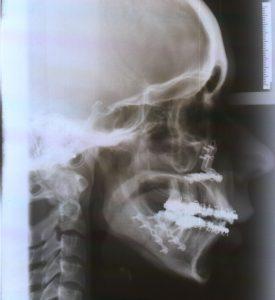

3. Posibles complicaciones de la cirugía.

Dentro de las complicaciones más frecuentes están las mordidas abiertas que se pueden producir, es decir, que se genere un hueco que no permita contactar los dientes incisivos anteriores. Cuando esto se produce en las primeras horas posteriores a la cirugía, requiere en muchas ocasiones la reintervención casi inmediata para restablecer el buen alineamiento de los segmentos óseos. Si la mordida abierta anterior se produce durante los siguientes meses, es necesario evaluar de manera objetiva la ATM, para descarta una reabsorción condilar que pudiese estar ocasionando esto.

La hipoestesia o perdida de la sensibilidad es una consecuencia directa de la cirugía difícilmente evitable por la manera es que se produce el alargamiento o acortamiento del segmento mandibular. Es importante comenzar desde el inicio con la pautas encaminadas al restablecimiento de la sensibilidad. Pero en ocasiones se pueden dañar algunos nervios que se sitúan cerca de la zona afectada por la cirugía por lo que es importante evaluar la evolución de la sensibilidad con el fin de descartar la lesion nerviosa irreversible.

Algún vaso dañado podría ser una complicación inmediata de la cirugía, que se repara de manera inmediata en la cirugía y que pone de manifiesto la importancia de la comunicación entre los distintos equipos, cirugía y fisioterapia, para poder conocer de primera mano cualquier suceso de importancia para establecer un correcto programa de recuperación que no dañe ni ponga en peligro ningún aspecto de la cirugía.

En ocasiones también se producen fracturas óseas indeseadas en la cirugía que necesitan ser restablecidas de inmediato.

Sabemos qué debemos recuperar entre los 40 y 50 milímetros de apertura alrededor de la 7ª semana después de la cirugía y es por tanto un objetivo a largo plazo, el restablecer de forma definitiva la movilidad mandibular en todo su rango de forma activa y pasiva.